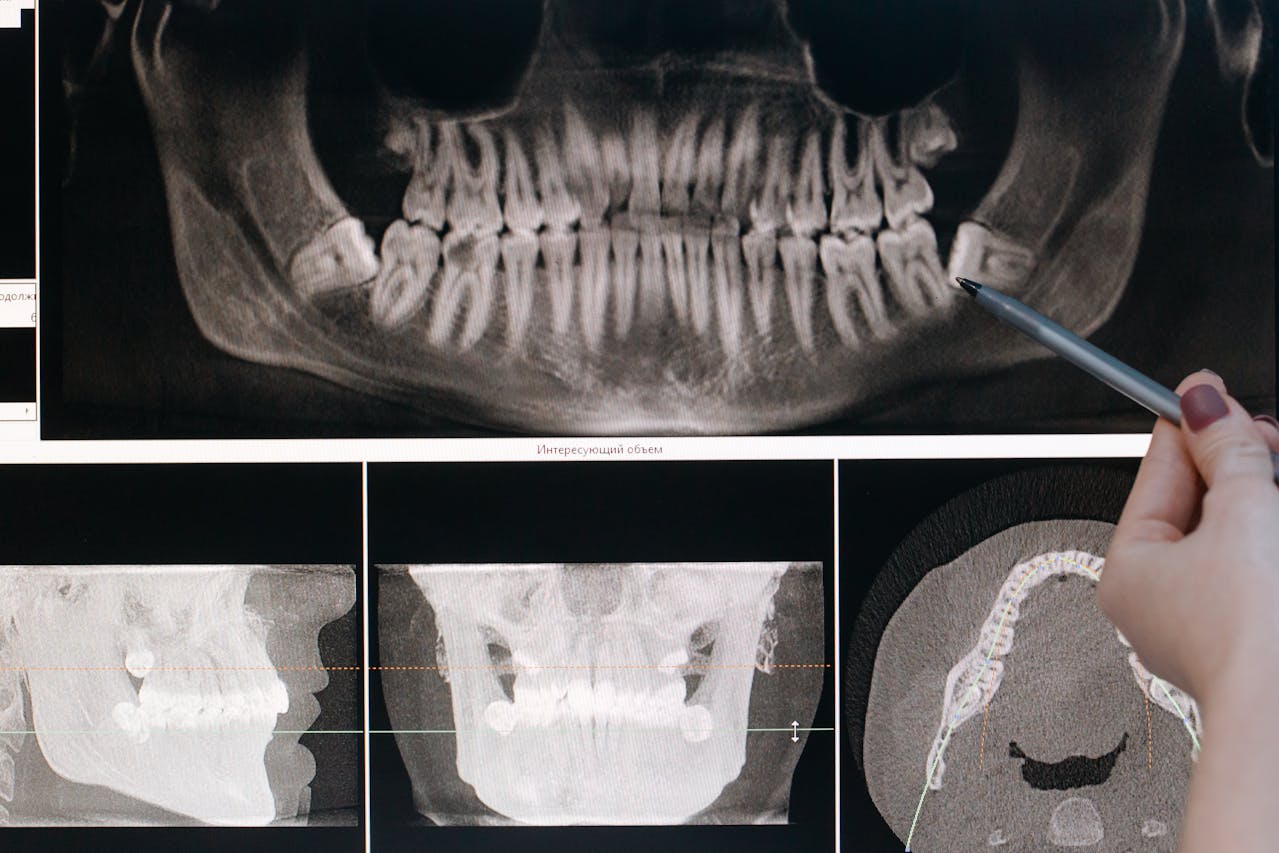

En nuestra clínica utilizamos tecnología de diagnóstico digital y escáner 3D, que nos permite analizar con exactitud la cantidad y calidad del hueso disponible antes de realizar cualquier procedimiento.

• Evaluar el volumen óseo con máxima precisión

• Diseñar un tratamiento completamente personalizado

• Aumentar la seguridad del procedimiento

• Mejorar la previsibilidad de los resultados

Esta tecnología nos permite ofrecer tratamientos más seguros, mínimamente invasivos y altamente eficaces.